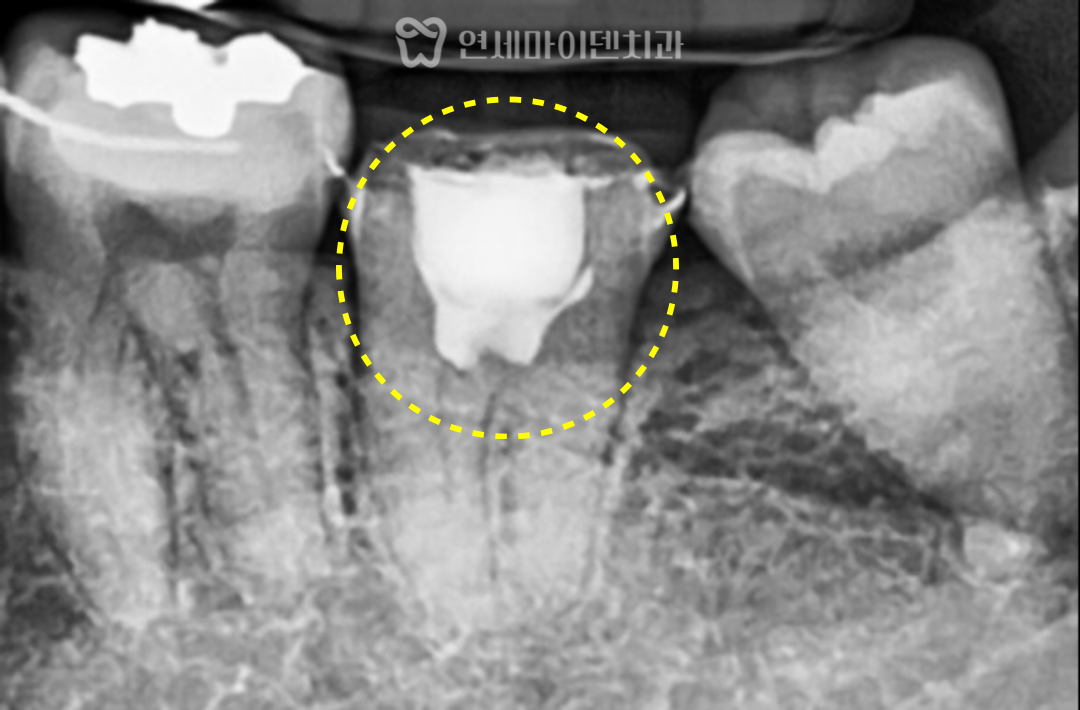

이번 치아는 C자 형태의

기형적인 근관 구조를 가지고 있었고,

미세현미경 하에서

해당 부위의 신경만 선택적으로 절단했습니다.

이후 칼슘실리케이트 제제,

흔히 MTA라고 불리는

생체 친화적인 재료로 충전하여

신경과 치근단 조직의 치유를 기대할 수 있도록 했습니다.